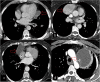

Hydatid cyst caused by the larval form of Echinococcus is a worldwide zoonosis. The lungs and liver are the most common sites involved. While the lung parenchyma is the most common site within the thorax, it may develop in any extrapulmonary region including the pleural cavity, fissures, mediastinum, heart, vascular structures, chest wall, and diaphragm. Imaging plays a pivotal role not only in the diagnosis of hydatid cyst, but also in the visualization of the extent of involvement and complications. The aim of this pictorial review was to comprehensively describe the imaging findings of thoracic hydatid cyst including pulmonary and very unusual extrapulmonary involvements. An outline is also given for the findings of complications and differential diagnosis of thoracic hydatid cyst.